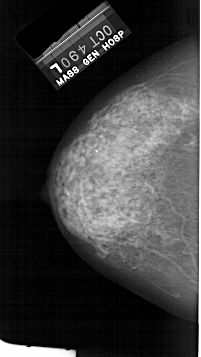

A_1384_1.LEFT_CC

LEFT_CC LINES 5701 PIXELS_PER_LINE 3211 BITS_PER_PIXEL 12 RESOLUTION 43.5 NON_OVERLAY